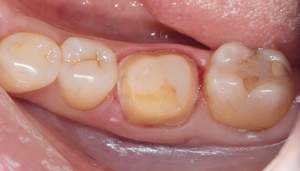

治療前

治療中

治療後